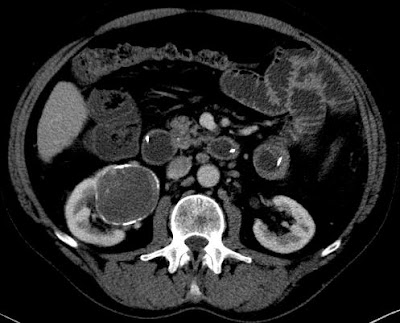

http://www.socrad.hu/upload/radiologia/magazine/274_279.pdf 5×0 3722372011.02.08. – UH -A jobb vese alsó pólusábn 5 cm-es cystosus képlet, melyen belül vaskos septumok látszanaka septumokban az ultrahangos kontrasztanyag már korai fázisban is...